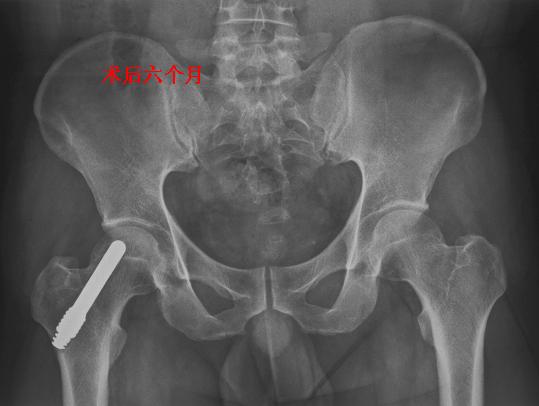

骨小梁金属avn重建棒钽棒治疗早期股骨头坏死

图片尺寸539x406